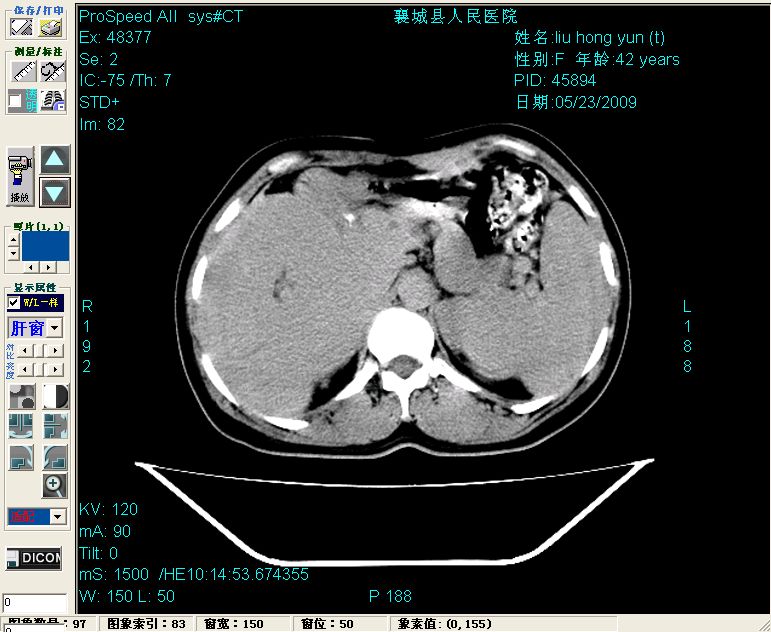

增强:

胰头部见结节状高密度影,其前方略可分辨扩强胆部管,平扫到增强始终有,但现在尚难与胃肠造影剂鉴别.

结合病史考虑,1现在引起黄疸体征的原因应该是胆总管胰段结石阻塞,建议局部胃肠造影剂排空后复查.

胆总管末端结石伴肝内胆管扩张合并结石!另:不除外合并胆系感染!

考虑:1、胆道结石伴肝内胆管扩张、积气;胆系感染!2、从平扫、增强片来看,不存在胆管肿瘤征象;3、提介建议:作为影像医师,在做一项检查之前应先熟悉临床医生的目的,象这个病例,检查前就不应喝高密度造影剂,而应充分喝好水就可,要不适得其反,反而较难判断胆总管下段是否有结石。